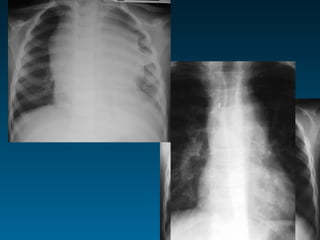

Οι συχνότερα χαμένες πνευμονίες